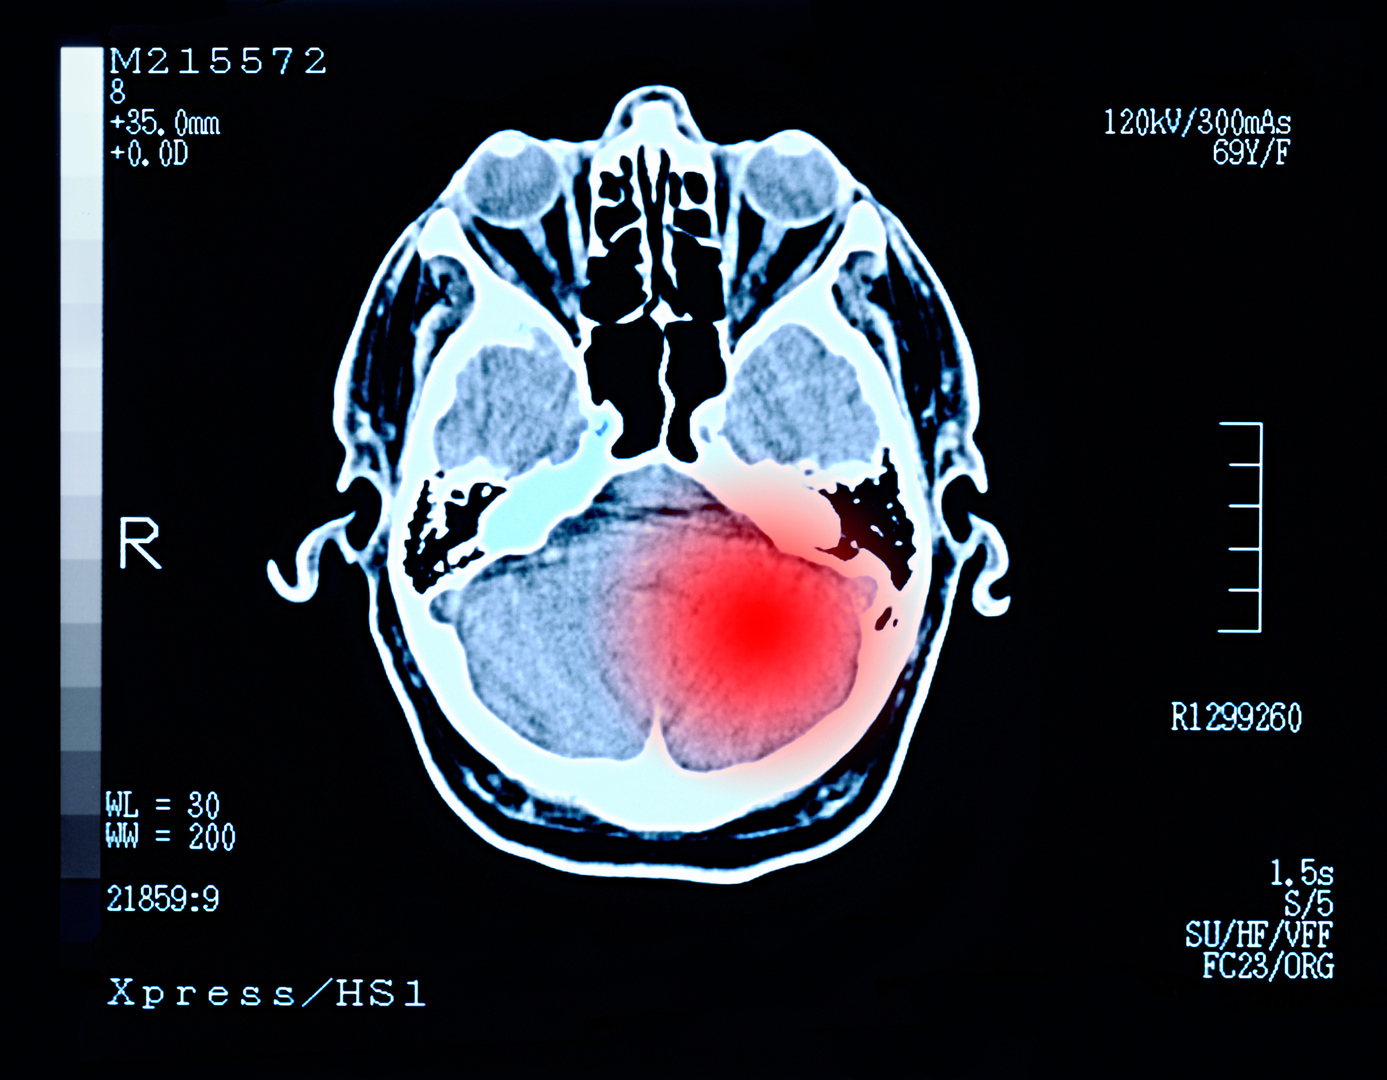

دراسة تكشف "نقطة ضعف خفية" في أخطر أورام الدماغ

حدد فريق دولي من العلماء "نقطة ضعف خفية" في دفاعات أحد أكثر أشكال سرطان الدماغ عدوانية، ما يشير إلى أن نظاما غذائيا متخصصا يمكن أن يلعب دورا حاسما في إبطاء نمو الورم.

وتوصل فريق من العلماء من خمس دول أوروبية، في دراسة نشرت بمجلة Science Advances، إلى أن الأدوية الشائعة من عائلة الستيرويد، والمستخدمة غالبا لعلاج الالتهاب المرافق للورم الأرومي الدبقي في الدماغ، تقوم بعمل مزدوج.

فهذه الأدوية لا تقلل الالتهاب فحسب، بل تعيد برمجة عملية التمثيل الغذائي للخلايا السرطانية بشكل جذري، وتحديدا في طريقة تعاملها مع فيتامين B3.

وهذا التغيير الاستقلابي، كما وصفه العلماء، يكشف عن "نقطة ضعف خفية" في بنية الورم. والأهم من ذلك، أن هذه الثغرة قابلة للاستغلال العلاجي، حيث وجد العلماء أن حرمان الخلايا السرطانية من حمض أميني محدد يسمى "الميثيونين" – عن طريق وضع المريض على نظام غذائي معد خصيصا يكون منخفضا جدا في هذا الحمض – يؤدي إلى تجويعها فعليا.

فبعد أن غيرت أدوية الستيرويد سلوكها، تصبح الخلايا السرطانية في أمس الحاجة إلى مشتقات هذا الحمض الأميني لمواصلة النمو والانتشار.

وبهذا، يطرح البحث استراتيجية علاجية جديدة تعتمد على التآزر بين دواء قديم ونهج غذائي مبتكر. فبدلا من الاعتماد على الدواء وحده، يتم الجمع بينه وبين تقييد غذائي محسوب، لخلق حالة من الحصار المضاعف على الورم.

ويأتي هذا الاكتشاف كنبأ سار في معركة طبية صعبة، إذ يتميز الورم الأرومي الدبقي بنموه السريع ومقاومته الشديدة للعلاجات التقليدية. وقد أعرب الخبراء عن تفاؤل حذر، مشيرين إلى أن مثل هذه الاكتشافات التي توفر أملا في إبطاء زحف الورم وتمنح المرضى وعائلاتهم وقتا ثمينا، هي بالضبط ما يحتاجه المجال الطبي.

وتتمثل الخطوة الحاسمة القادمة في نقل هذه النتائج الواعدة من أروقة المختبرات إلى أسرة المرضى، عبر تجارب سريرية دقيقة تختبر فعالية وأمان هذه المقاربة العلاجية الجديدة.